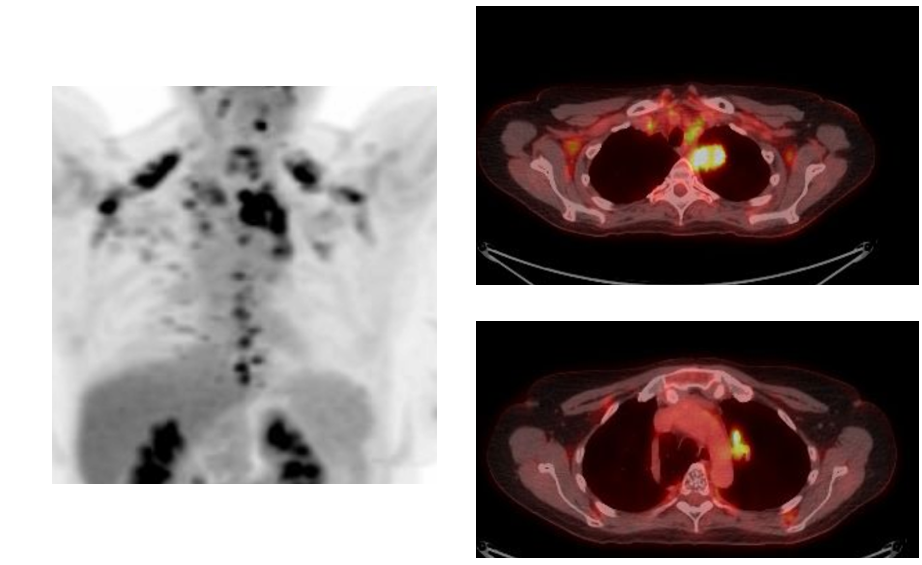

- PET images suspicious for mediastinal lymphadenopathy (SUV 3.5-5.0) and left hilum (SUV 11.0) but EBUS negative for malignancy in levels 4L, 4R, 7, 10L, and 10R.

PET Scan